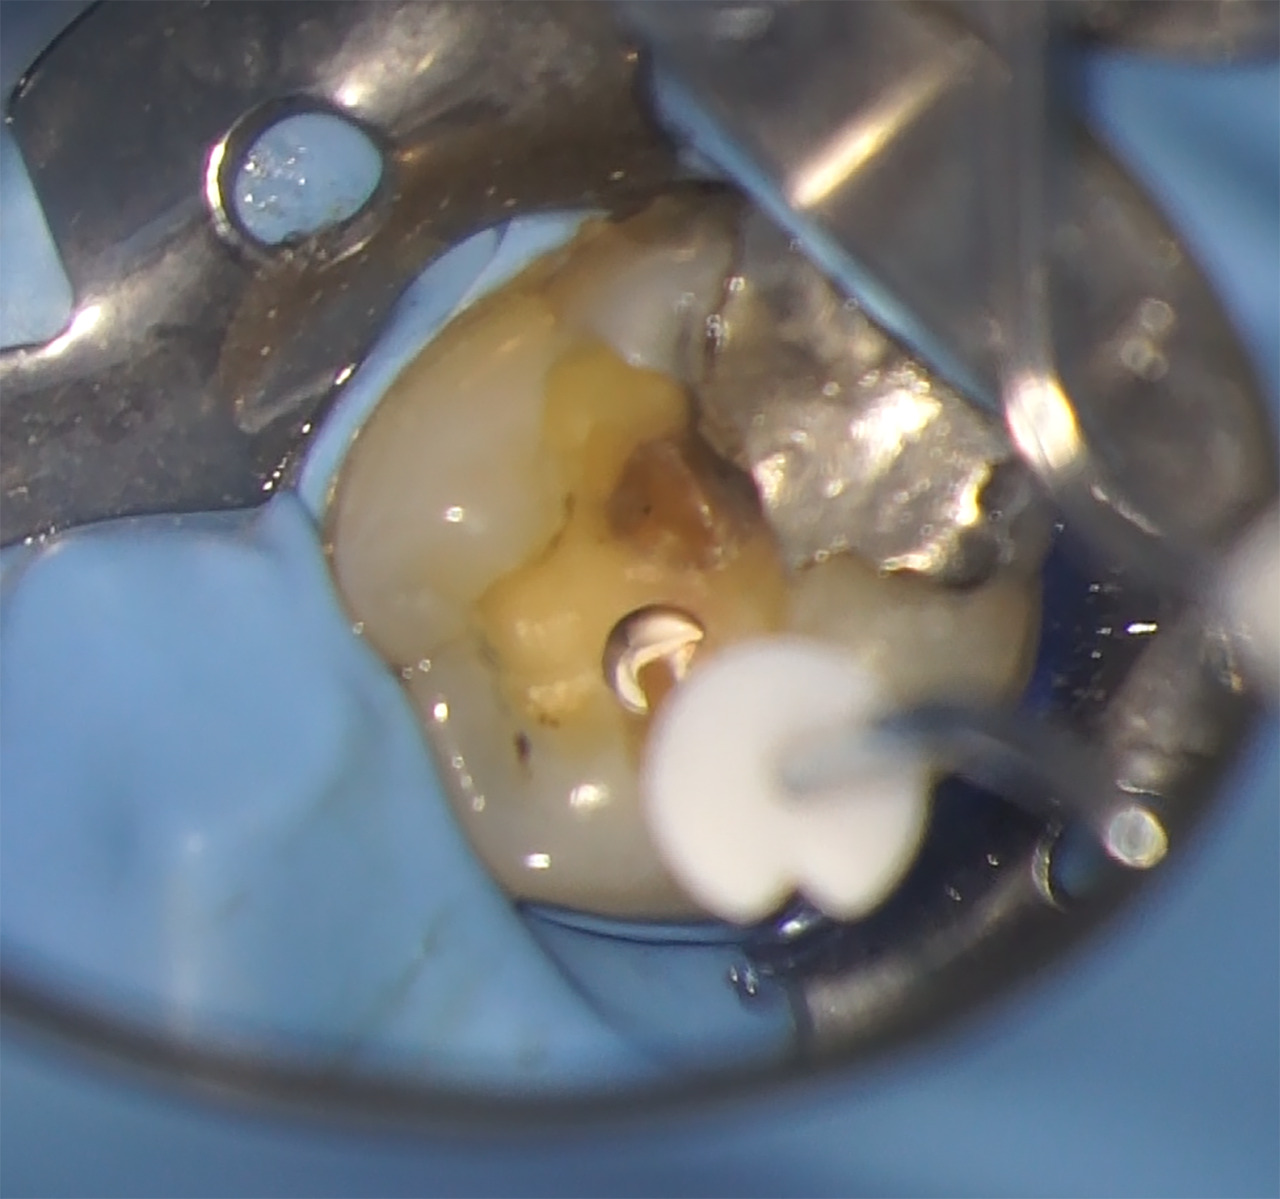

Malgré les difficultés rencontrées pour obtenir le séchage du canal (Fig.10), il a finalement été possible de se remettre dans des conditions adéquates pour l’obturation, dans la même séance.

Le canal a donc été séché avec des cônes de papier Slim Shaper (Zarc, Espagne) et l’obturation conduite avec une biocéramique.

Le Neosealer Flow (Zarc by Avalaon, Espagne) est injecté directement dans le canal et un cône de gutta adapté au système a été mis en place afin de finir l’obturation (Fig.11). Le cône a enfin été sectionné à l’entrée du canal puis compacté avec un fouloir Prexo M (Deppeler, Suisse) afin de créer un bouchon coronaire.

Fig.10 : Séchage du canal avant obturation.